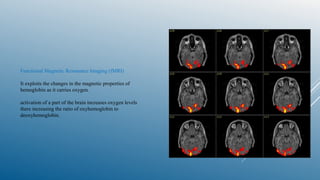

Functional Magnetic Resonance Imaging (fMRI)

It exploits the changes in the magnetic properties of

hemoglobin as it carries oxygen.

activation of a part of the brain increases oxygen levels

there increasing the ratio of oxyhemoglobin to

deoxyhemoglobin.